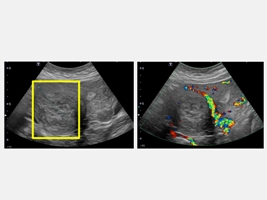

45歲的魏女士因為近半年來出現下腹部悶痛,所以到仁愛長庚合作聯盟醫院(大里仁愛醫院)婦產科林玉珊醫師門診求診,檢查後發現有下腹部悶痛合併壓迫症狀,竟然有7公分的肌瘤。經採用達文西機械手臂系統結合經陰道自然孔手術,於術後一週後即返家休養。由於手術並未在腹部留下傷口,讓魏女士感到非常驚訝,林玉珊醫師表示,傷口只是藏在看不到的地方,這不只是手術傷口變小,更代表病人能更快回到自己的生活與角色中。

林玉珊醫師指出,傳統腹腔鏡手術雖屬微創方式,但仍需在腹部開設多個小切口。經陰道自然孔手術是利用陰道作為自然通道進入骨盆腔,完全免除腹部傷口。第四代達文西機械手臂系統的高解析3D影像讓骨盆腔結構更清楚,機械手臂能在極狹小的空間中完成精細的分離與縫合。病人出血量少、疼痛感輕微,大多數人隔天即可下床,恢復速度比傳統手術明顯更快。